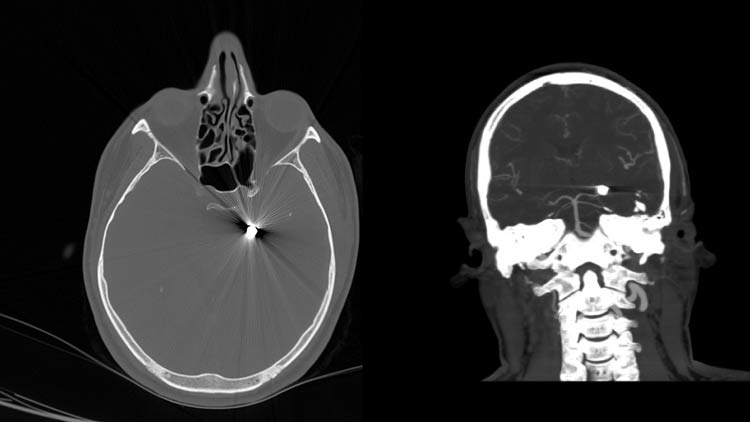

തലയില് തുളഞ്ഞുകയറിയ വെടിയുണ്ട റോബോട്ടിക് ശസ്ത്രക്രിയയിലൂടെ നീക്കം ചെയ്തു